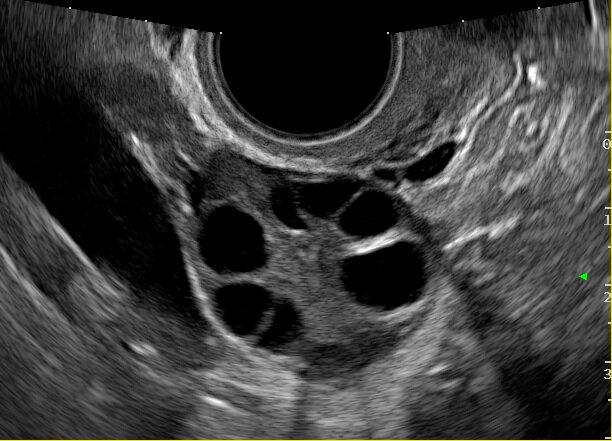

Los avances en este capítulo son extraordinarios. Bien empleados, puede decirse que muy pocas mujeres quedan sin diagnóstico en el caso de presentar patologías. La antigua "laparotomía exploradora" como método para establecer la causa de una enfermedad ginecológica, ha desaparecido en la actualidad. Ya no se concibe operar sin diagnóstico previo. Los avances continuos en el campo de las imágenes, nos permite conocer con creciente precisión, la condición de los órganos genitales pelvianos femeninos. La ecografía es el primer gran auxiliar, indispensable casi, para evaluar el estado anátomofuncional de útero y ovarios por vía abdominal transvesical en mujeres delgadas y sin relaciones sexuales o por vía transvaginal, en aquellas con actividad sexual que aceptan esta vía o en obesas, donde el espesor de la pared abdominal dificulta una buena visualización. En las figuras 1, 2, 3 4, 5 observamos ejemplos de genitales normales y de alguna patología. Hoy día la técnica denominada 4D brinda imágenes excelentes por lo que es empleada con frecuencia en el estudio morfológico del feto en su tercer trimestre.